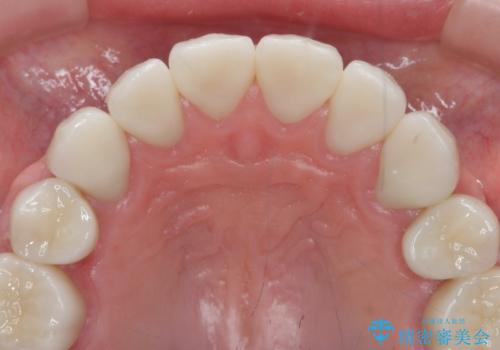

神経を温存したまま仮歯に置き換え、噛み合わせの安定を確認したのちに すり減りに強いジルコニアクラウンで最終的な仕上げを行います。

歯の形態・色調を大きく変更する場合ジルコニアクラウンによる治療が耐摩耗性・審美性の観点から推奨されます。